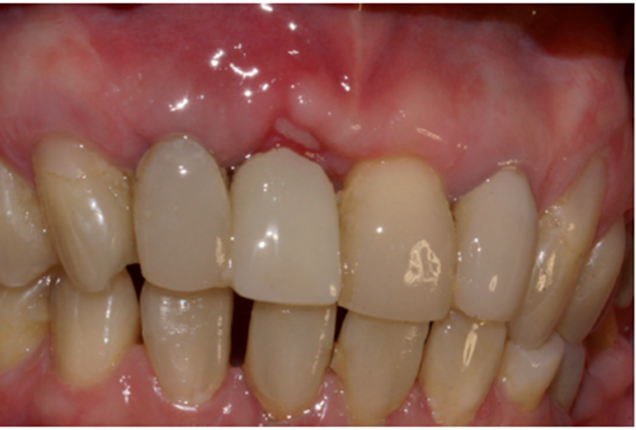

No laboratório, o técnico de prótese posicionou o pilar Ideale angulado no modelo (Figura 27) e confeccionou um incisivo central parafusado sobre ele, utilizando a coifa de provisório que o sistema oferece (Figura 28). Uma vez obtido o provisório, o cicatrizador voltou a ser removido e o pilar Ideale e o provisório foram instalados em boca (Figuras 30 e 31). O pilar foi torqueado em 20 Ncm e o parafuso da coroa foi torqueado em 10 Ncm. Após 15 dias, o provisório foi removido e observou-se o perfeito perfil de emergência que havia sido obtido (Figura 33). Neste novo momento foi posicionado sobre o pilar um transferente plástico de moldeira fechada do pilar Ideale, sendo que tanto o pilar como o dente 12 foram moldados (Figura 34) para a confecção de copings e posterior a aplicação da cerâmica (Figura 35).

Após a conclusão desses passos pelo laboratório, a prótese do elemento 12 foi cimentada com fosfato de zinco e a prótese sobre o pilar Ideale foi parafusada e torqueada a 10 Ncm (Figura 36). O orifício de acesso foi restaurado com resina fotopolimerizável (Figura 37). Uma radiografia final foi realizada, demonstrando o perfeito assentamento da coroa sobre o pilar Ideale.